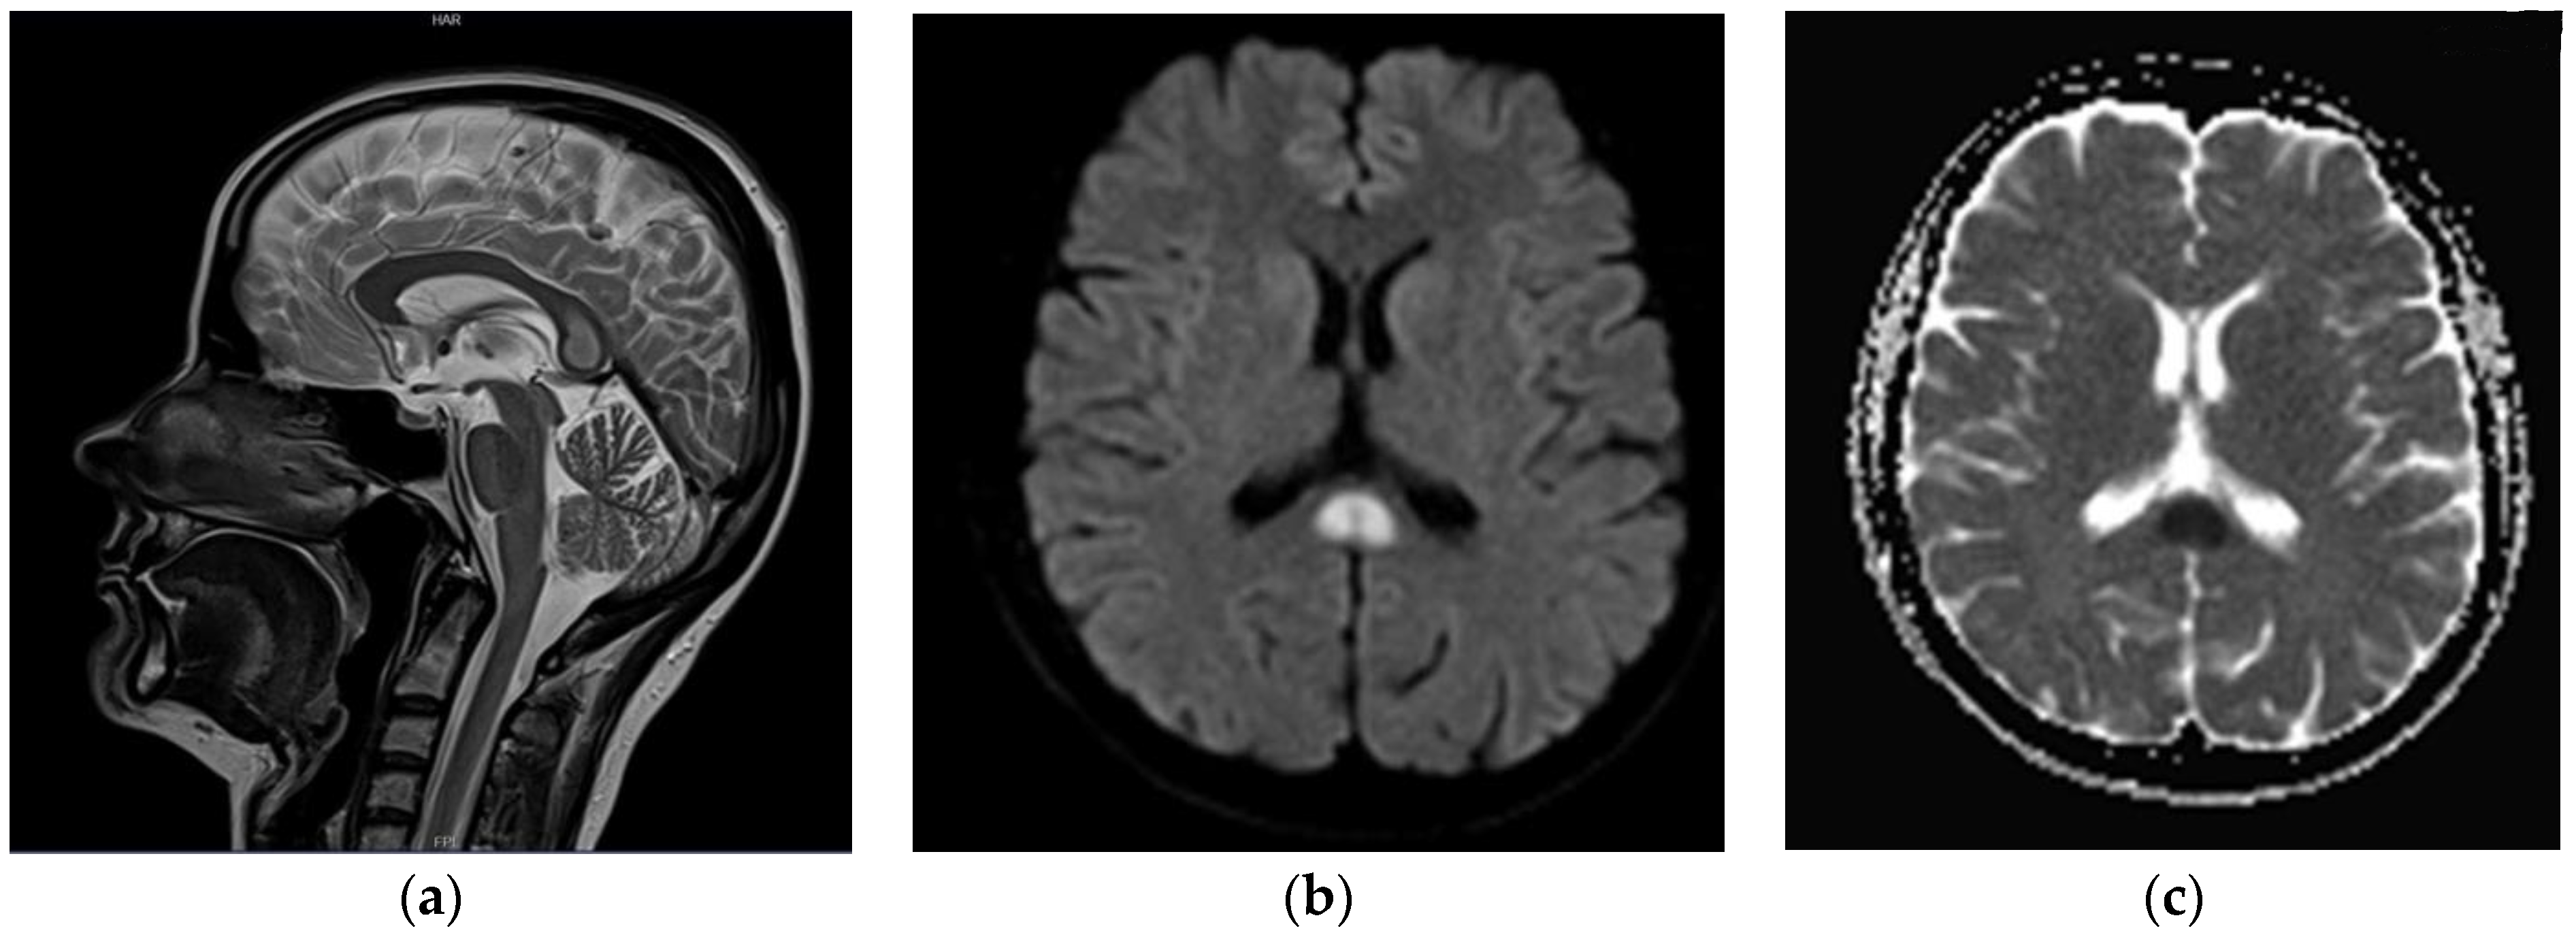

A follow-up head MRI was performed (end of June 2020), which revealed an isolated, focal lesion of the SCC (15 × 10 × 15 mm) that was hyperintense on T2w images, with diffusion restriction on diffusion-weighted images; no pathological contrast enhancement was seen (Figure 2). A differential diagnosis of the lesion comprised: active demyelinating plaque, Marchiavafa-Bignami syndrome (MBD) and ischemic lesion. The patient underwent extensive laboratory testing, including a coagulation panel, vitamin B12 concentration, electrolytes and inflammatory markers; no abnormalities were found (Table 1). She denied excessive alcohol consumption. The diagnosis of symptomatic epilepsy was maintained in the light of the above (2 July 2020); antiseizure medications, in particular valproic acid (target dose 300 mg twice daily), were started again.

Figure 2.

(a) T2-weighted (blade) images in sagittal plane; (b) DWI b = 1000 axial images; (c) corresponding Apparent Diffusion Coefficient (ADC) map. Well-demarcated, T2 hyperintense lesion (15 × 10 × 15 mm) within splenium of the corpus callosum (a,b) with apparent diffusion restriction on DWI/ADC images (c).